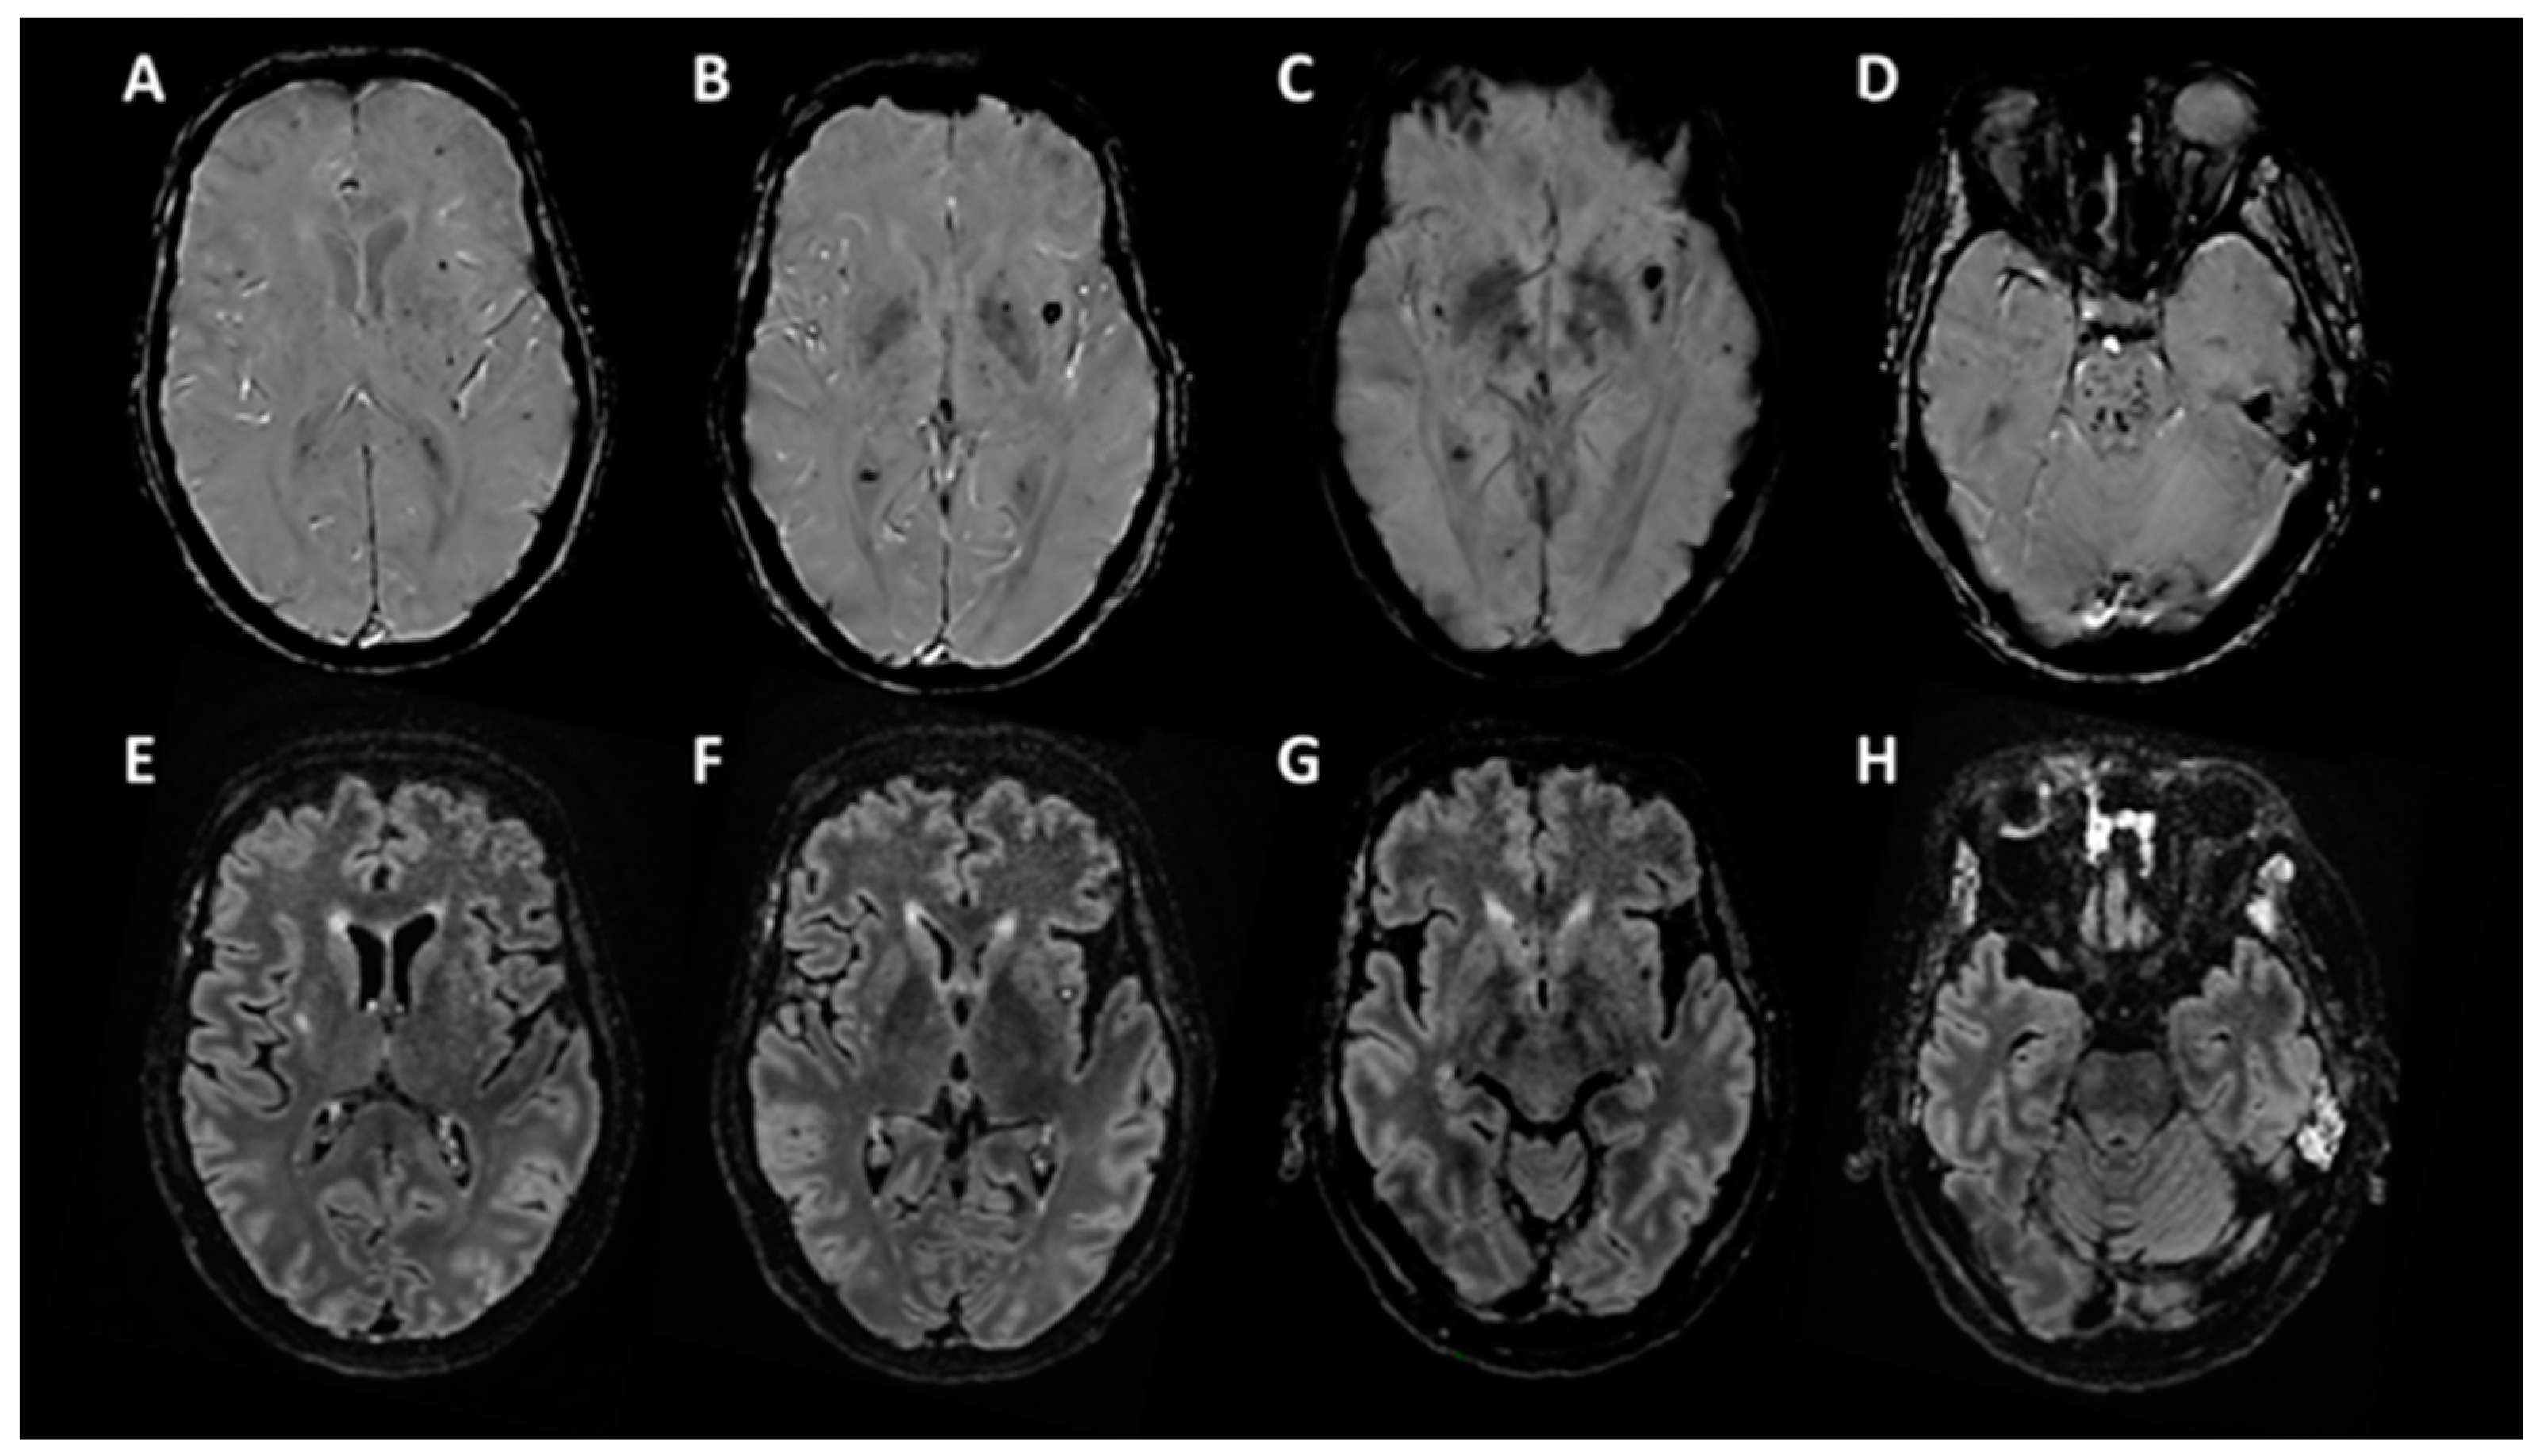

At day 55, clinically the patient still unresponsive (Glasgow coma scale = 4/15 (E2-V1-M1), Full outline of unresponsiveness (FOUR) score = 6 (E1-M0-B4-R1), coma recovery scale revised (CRS-r) = 2/23 (0-1-0-0-0-1)). A brain MRI at day 55 (Figure 1) showed multiple small haemorrhagic lesions in the pontine tegmentum (D) and the left and right subinsular regions that notably include claustrums, as well as deep ganglia, corpus callosum, and cortico-subcortical regions (A–C). There were few signal abnormalities on FLAIR (E–H) and no associated contrast enhancement.

Figure 1.

Brain MRI, T2 Star Susceptibility Weighted ANgiography (SWAN) sequence (A–D), and FLAIR sequence (E–H).